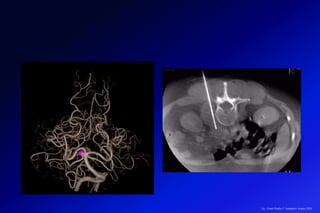

PET / CT 128 Cortes

SPECT / CT128

Reducción de la dosis de TC Reconstrucción

Iterativa ASIR (30% -50%)

Fusión de Imágenes de

Medicina Nuclear y

Tomografía